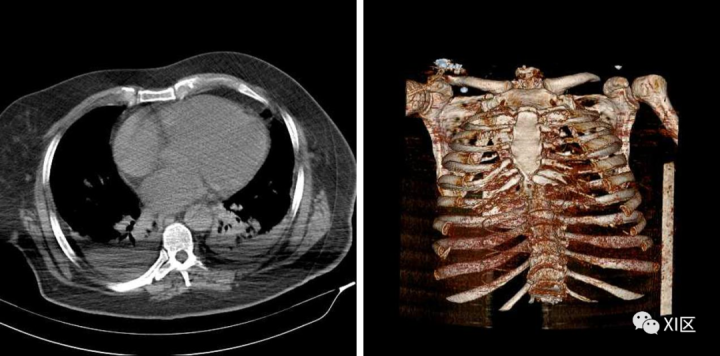

暂时性造影剂中断(Transient interruption of contrast)

胸部的增强轴位CT图像显示上腔静脉、升主动脉和降主动脉造影剂强化,而肺动脉主干相对未增强。